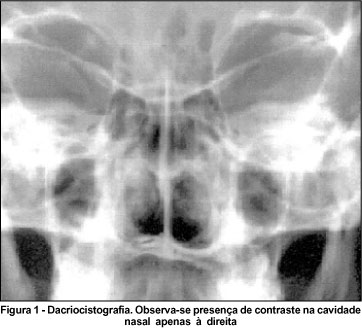

Na propedêutica de vias lacrimais, a paciente apresentou retenção de contraste importante apenas em OE (Milder +) com obstrução de vias lacrimais aparentemente ao nível de canal comum uma vez que a irrigação mostrou refluxo de soro por ambos os canalículos sem presença de secreção. A dacriocistografia evidenciou vias lacrimais sem alterações à direita e, à esquerda, não foi observado aparecimento de contraste na via lacrimal assim como o saco lacrimal apresentava-se aparentemente normal (Figura 1).